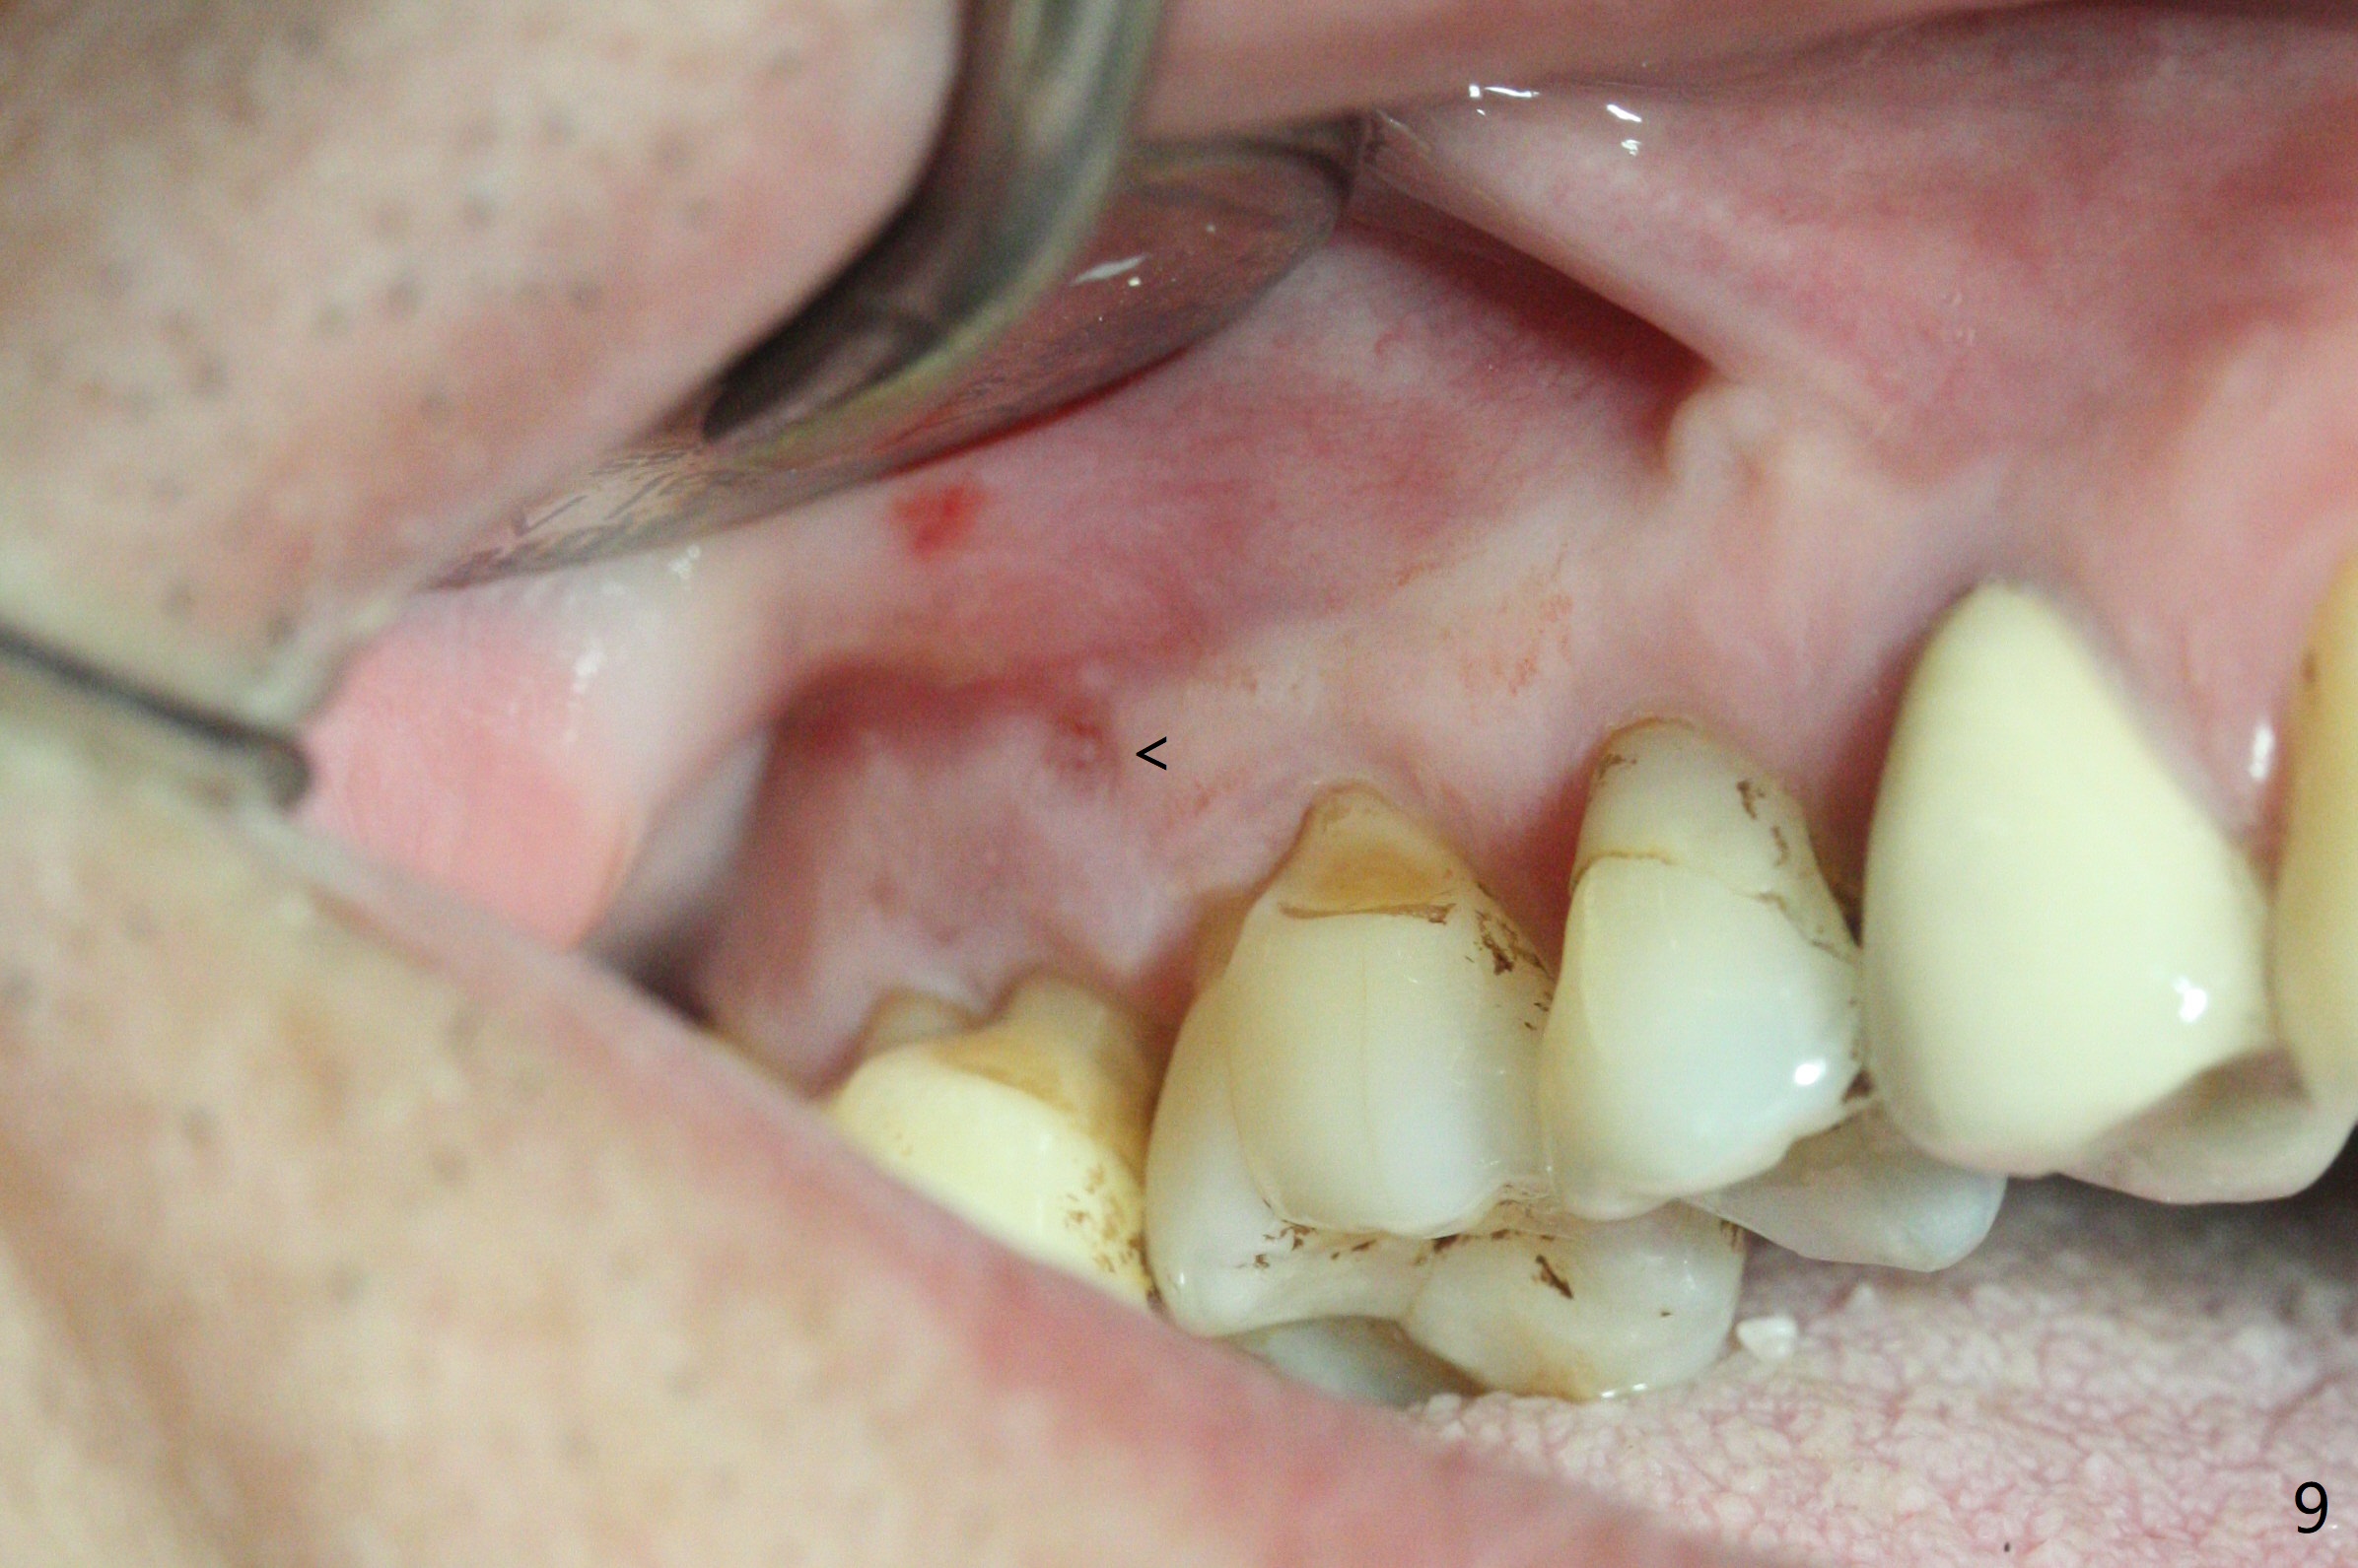

Two days post #31 implant placement, the patient returns for orthodontic intrusion of the tooth #2 with mini-implants (Fig.1). The palatal cusps have been trimmed (Fig.2 ^), since they almost contact a healing abutment at #31(*, Fig.3). Two mini-implants are to be placed mesiobuccal and distopalatal to the affected tooth. After minimal injection of Lidocaine, a 1.6x6 mm Tomas implant is placed in full length mesially (Fig.4), while the other (1.6x8 mm) half way (Fig.4). Following change in implant site mesially (Fig.6 >), the implant is half inserted (Fig.5). It appears that the tip of the distal implant is toward the tooth #1 (Fig.5). After withdrawing the implant partially, it is re-directed to apparently ideal trajectory (Fig.7). Ideally the mesial implant (Fig.8) should have been placed partially initially (Fig.4,5,7) so that the trajectory could have been able to be changed.

The buccal implant becomes loose in 2-3 months. When the wound heals (Fig.9 <), a 1.6x`10 mm implant is placed with the help of PAs for trajectory (Fig.10,11) and in the nonkeratinized gingiva (higher, the crestal bone may have been traumatized by previous implant placement, Fig.12). Two months later, the tooth #2 is partially intruded (Fig.13). A provisional (Fig.14 P) is fabricated in the osteointegrated implant at #31 with supraocclusion so that the remaining dentition has no occlusal contact (*). The periodontally compromised tooth #2 becomes in buccoversion in 2 months. The provisional is removed, while a lingual button is placed in the buccal surface of the tooth #2 (Fig.15). With power chain attached to the lingual mini-implant, the tooth #2 is lingualized in 2 months. The provisional and the implants are reused for final intrusion (Fig.16). The treatment is nearly 11 months. The buccal implant, although placed in the movable mucosa, remains stable and healthy (Fig.17). The tooth #1, as a guiding plane (to prevent #2 from distalization during intrusion), is not extracted after intrusion is completed.